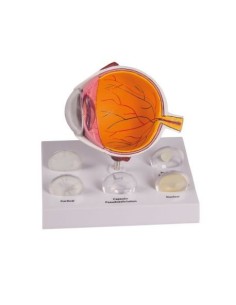

3B Scientific, modello anatomico di occhio, ingrandito di 5 volte, in 6 parti F10

3B Scientific, modello anatomico di occhio patologico, ingrandito di 5 volte F17

3B Scientific, modello anatomico di occhio ingrandito 5 volte, in 6 parti VJ500C

3B Scientific, modello anatomico di occhio, ingrandito di 5 volte, in 7 parti F11

3B Scientific, modello anatomico di occhio, ingrandito di 5 volte, in 8 parti F12

3B Scientific, modello anatomico di occhio ingrandito 3 volte, in 6 parti F15